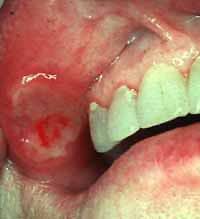

Loli-pop Mesaj tarihi: Ağustos 6, 2005 Mesaj tarihi: Ağustos 6, 2005 [spo1=fotoğraflar tatsız biraz, ona göre] Memorial Hastanesi Dermatoloji Bölümü doktorları "Behçet Hastalığı" ile ilgili bilgi verdi: Behçet Hastalığı, 1937 yılında ünlü Türk doktoru Ord.Prof.Dr. Hulusi BEHÇET tarafından tanımlanan ve tıp dünyasının "Behçet Hastalığı" olarak kabul ettiği bir hastalıktır. Behçet Hastalığı, bir virüsün yol açtığı düşünülen, bütün sistemleri tutabilen, hastalığın seyri sırasında iyileşme ve kötüleşme dönemleri olan ve zaman ilerledikçe giderek ilerleyen bir hastalıktır. Hastalığın olağan başlangıcı, 20-40 yaşları arasındadır ve kalıtım yoluyla bir kuşaktan diğerine geçebilmektedir. Hastalığın tanımlanmış belirtileri; 1. Ağızda tekrarlayan ağrılı, kızarık, zımba ile delinmiş gibi şekli olan "Aft" denilen bazen çok sayıda olabilen yaralar.Büyüklükleri 1-2 mm'den 1-2 cm çapına kadar değişebilir.Hastaların %97-100'ünde bu belirti vardır.Hastalığın diğer belirtilerinden yıllar önce haberci olarak çıkabilir.3-10 gün arasında kendiliğinden iyileşebilir. 2. Genital bölgede,ağızdaki yaraların benzeri yaralar da görülür.Bu belirti,hastaların %80-90'ında vardır; ancak iyileşme sırasında iz bırakırlar ve daha uzun sürede iyileşirler. 3. Gözün değişik tabakalarını tutan iltihaplı oluşumlar ise, hastalığın en ciddi belirtileridir.Bu oluşumlar hastaların %50'sinde bulunmaktadır.Bu aş amada, hastalık optik siniri tutabilir ve bu da körlüğe neden olabilir.Tekrarlayıcı bir karaktere sahip olan Behçet hastalığı, yetişkin erkeklerde, kadın ve yaşlılara göre daha ağır seyretmektedir. Sürekli yapılan bilimsel çalışmalarda, hastalığın yalnız bu 3 belirtisi (etkisi) ile kalmadığı, hemen hemen bütün vücut sistemlerini tutan pek çok belirtisiyle çok daha önemli bir hastalık olduğu saptanmıştır. Yapılan birçok çalışmaya rağmen, hastalıkta kesin çözüm sayılabilecek bir tedavi henüz tam olarak bulunamamıştır. Ancak hastalığın belirtilerini engelleyen, ilerleyişini durdurmaya yönelik birçok ilaç ve tedavi yöntemli de geliştirilmiş ve kullanılmaya devam edilmektedir. "Türkiye'nin İlk Özel Behçet Hastalıkları Merkezi" olma onurunu taşıyan Memorial Hastanesi Behçet Hastalıkları Merkezi'nde konun uzmanlarından oluşan ekibiyle hizmet vermektedir.[signature][hline]- Aya inemiyoruz? - Neden, modül mü bozuldu? - Yok, Kültür Bakanlığı sit alanı ilan etmiş, bilet almamız lazımmış...[/spo][Bu mesaj Nefr tarafından 07 Ağustos 2005 15:19 tarihinde değiştirilmiştir]

Cd- Mesaj tarihi: Ağustos 7, 2005 Mesaj tarihi: Ağustos 7, 2005 Cinsel organda afta benzer yaralar çıkarsa veya gözünüzde bi rahatsızlık olursa (o nası bi rahatsızlık tam olarak bilmiyorum ilginç bi adı vardı) ayrıca bş kahç belirtisi daha var. Ağız yaraları Ağız yaralarına hemen hemen her hastada rastlanır ancak % 1 - 3 gibi az bir kısım hastada ağızda yara şeklinde bir belirti görülmeksizin hastalığın diğer belirtileri görülebilir. Genellikle ağızdaki yaralar hastalığın ilk belirtileridir ve diğer belirtiler ortaya çıkmadan yıllarca aft yakınması bulunan hastalar az değildir. Behçetteki ağız yaraları, tekrarlayıcı basit aftlardan ayırd edilemez ise de çok sayıda olmaları ve daha sık nüks etmeleri gibi farklılıklar vardır. Behçette aftlar genellikle ayda bir veya birkaç kez tekrarlar ve bir kaç gün içersinde iyileşirler. [spo1=Diğer Belirtiler]Cinsel Bölge Yaraları Behçet hastalığının diğer bir belirtisi de genital bölgede tekrarlayan yaralardır. bu yaralar küçük, deriden kabarık kırmızılık veya sivilce halinde başlar ve bunu, çabucak zımba ile delinmiş görünümde ve yavaş iyileşen yaranın gelişmesi izler. Bu yaralar hemen her zaman yerlerinde iz bırakarak iyileşirler. Genital bölge yaraları aftlara göre sayıca daha az ve daha uzun sürede iyileşirler. Deri Belirtileri Behçet hastalığında, koltuk altları ve kasıklar gibi büyük kıvrım yerlerinde de benzer yaralara zaman zaman rastlanabilir. 1. Kırmızı ve ağrılı yumrular şeklinde oluşumlar. 2. Sivilce benzeri belirtiler. 3. Deri damarlarının hastalanmasıyla ilgili belirtiler. Göz Belirtileri En önemli organ tutulmalarından biri olan gözdeki iltihaplanma hastaların yarısında tespit edilir. Gözde kanlanma ve bulanık görme şeklinde kendini gösterir. Erkeklerde ve genç kisilerde göz belirtileri daha sık ve daha ağır seyrederken, kadınlarda ve yaşlılarda daha seyrek ve daha hafiftir seyreder. Göz belirtileri bazan körlüğe kadar gidebilir. Bu belirtilerin dışında Behçet hastalarının hemen hemen yarısında eklem ağrısı ve eklemlerde şişme gibi şikayetler, beyin hastalıkları, böbrek iltihabı, damar tıkanma ve genişlemeleri de görülebilir. Behcet hastalığı daha çok 20-30 yaşlarda ve erkeklerde görülür. Türkler, Araplar, Yahudiler, Ermeniler ve Japonlarda daha sık görülür. Behçet hastalığının en karakteristik özelliklerinden birisi ataklar halinde seyretmesidir. Yaşla birlikte hastalığın aktivitesi azalır. Behçet hastalığının nedeni bilinmemektedir. Tedavi hastalığın etkilediği organa göre değişir. Tedavi kesinlikle doktor kontrolünde yapılmalıdır. Genetik biliminde sağlanacak gelişmeler Behçet hastalığının tedavisinde yeni ufuklara yol açacaktır. Behçet hastalığının en tipik özelliğinin ağızda tekrarlayan yaralar olduğu unutulmamalı ve bu yakınmaları olan hastaların mutlaka Behçet hastalığı yönünden araştırılması gereklidir. [/spo] Ağız yaralarının yanında bu belirtilerin en az ikisi daha varsa doktora görünün. Fakat herkesin ağızında aft çıkıyo o açıdan panik yapmayın. Not:Bu arada bende behçet yok yani yukarda sanki varmış gibi yazmışım.[signature][hline][Bob Marley] Egoist Ben!!!(Ünlemlere de bak) Gazeteci-Bir "rastaman" olmam için ne yapmam gerek? Bob Marley-Yeniden doğmalısın... [Bu mesaj Cd- tarafından 07 Ağustos 2005 17:32 tarihinde değiştirilmiştir]